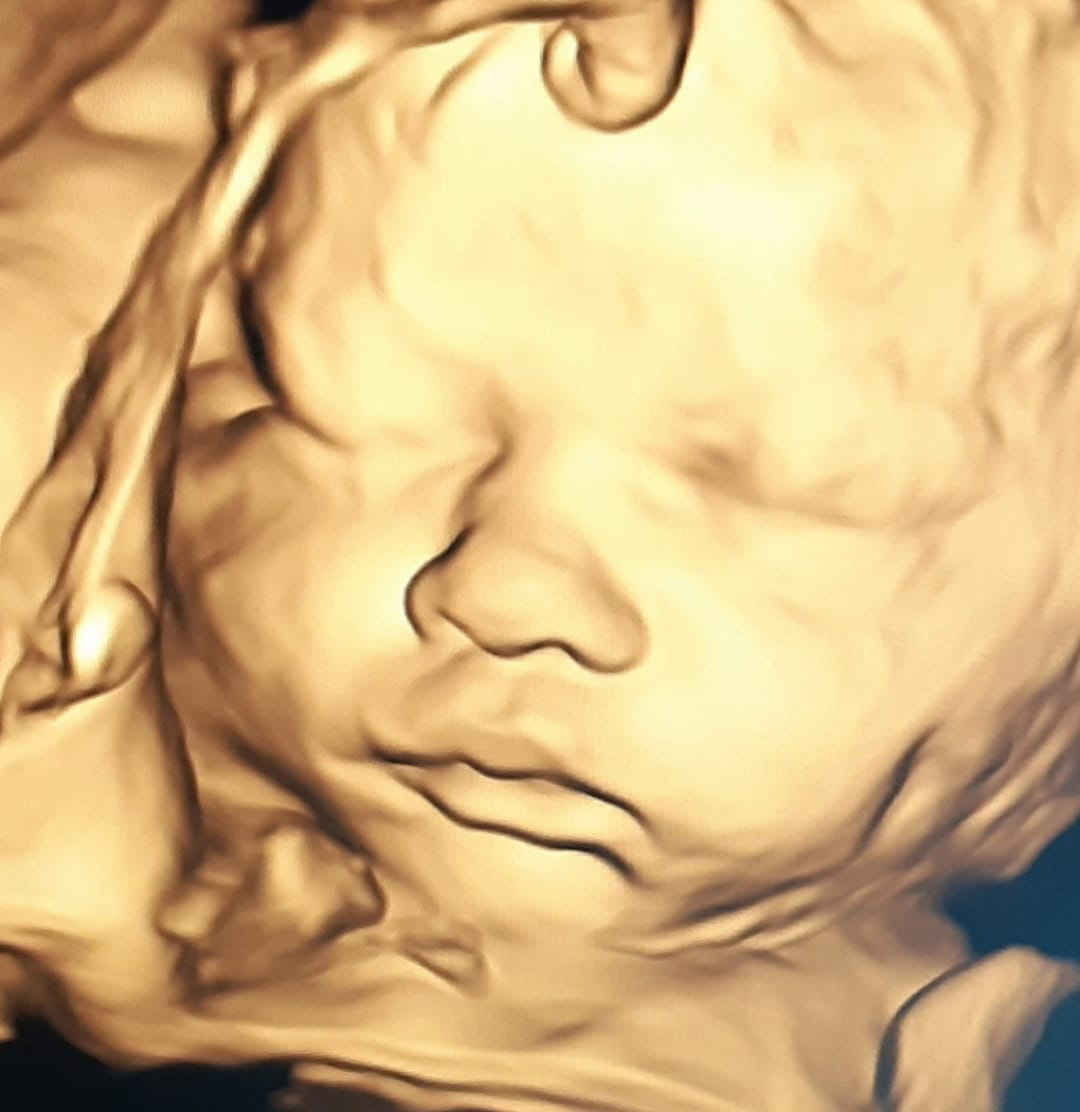

L'échographie 3D et 4D

L’échographie en 3D (image fixe) ou 4D (le foetus est en mouvement) peut être réalisée à partir de 22 SA afin de vous permettre de visualiser le visage de votre bébé, mais seulement si vous le souhaitez.

Elle n’est pas toujours possible selon la position du bébé. La qualité de l’image dépendra aussi de l’échogénicité de votre paroi abdominale.